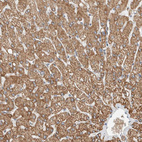

Immunohistochemical staining of human liver shows strong cytoplasmic positivity in hepatocytes.